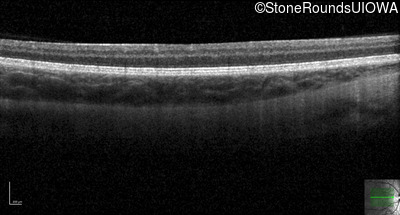

Optical Coherence Tomography - Right - 20/125

Exemplar / OCT Stack

OCT Stack